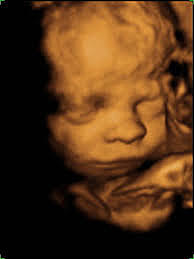

• ECOGRAFÍA TRIDIMENSIONAL

ECOGRAFÍA TRIDIMENSIONAL

Primera ecografía tridimensional en Austria con un aparato de la casa Kretz. Reconstrucción a partir de 780 imágenes de ecografía bidimensional obtenidas en los 3 planos del espacio, que se computarizan y permite la reconstrucción de la imagen en 3 dimensiones.

Es magnífico el gran avance en el diagnóstico de enfermedades prenatales. Samaranch, M. (2016). Historia de las ecografías. Agosto 25, 2019, de Ecografías 3D Sitio web: http://www.ecografias3d.com/es/historia